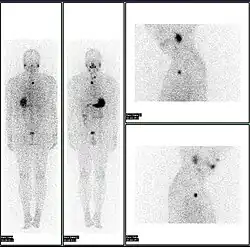

A nuclear medicine whole body bone scan. The nuclear medicine whole body bone scan is generally used in evaluations of various bone-related pathology, such as for bone pain, stress fracture, nonmalignant bone lesions, bone infections, or the spread of cancer to the bone.

A nuclear medicine parathyroid scan demonstrates a parathyroid adenoma adjacent to the left inferior pole of the thyroid gland. The above study was performed with Technetium-Sestamibi (1st column) and iodine-123 (2nd column) simultaneous imaging and the subtraction technique (3rd column).

A nuclear medicine SPECT liver scan with technetium-99m labeled autologous red blood cells. A focus of high uptake (arrow) in the liver is consistent with a hemangioma.